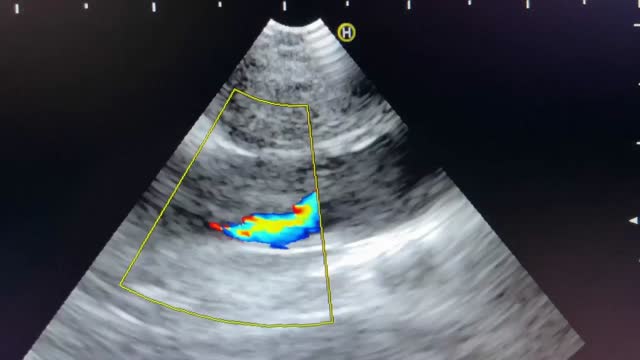

The patient's admission was prompted by symptoms including respiratory failure, asthenia, and atypical chest pain persisting for a week. A chest X-ray revealed mediastinal widening. In response to these findings, a computed tomography (CT) scan was performed, unveiling the presence of a solid mass in the mediastinal region and the right superior hilar area. This mass exhibited close proximity to the right tracheal margin, the right brachiocephalic trunk, the right main pulmonary artery, as well as the ipsilateral superior lobar pulmonary arteries and veins, suggesting possible infiltration (Fig. 1). Consequently, an endobronchial ultrasound-guided transbronchial needle aspiration (EBUS-TBNA) was conducted, enabling the diagnosis of the mass as lung adenocarcinoma and the identification of partial thrombosis within the superior vena cava, as illustrated in Video A.

It is noteworthy that venous thromboembolic disease affects approximately 20% of cancer patients.1 Although the utilization of EBUS for diagnosing central pulmonary embolism in patients with contrast allergies has been documented, there are no reported instances of superior vena cava thrombosis.2 This underscores the importance of bronchoscopists acquiring proficiency in recognizing such findings.